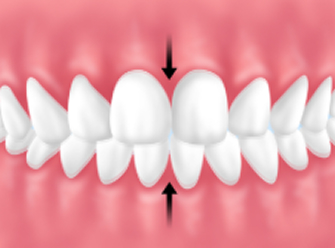

│グラインディング(歯ぎしり)

│クレンチング(食いしばり)